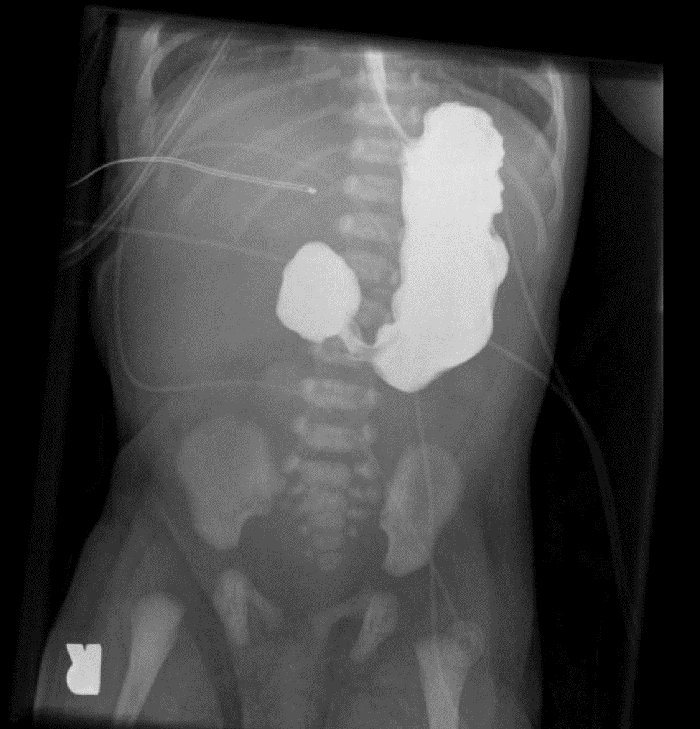

Our patient was extubated to room air the next day, and although she passed meconium after surgery, nasogastric tube (NGT) output remained high and on DOL 4 an upper gastrointestinal contrast study confirmed the suspected duodenal atresia (Figure 2). As the infant was now very stable, we returned to the operating room and she was intubated for surgery; intraoperatively she was found to have an annular pancreas and duodenal atresia. A duodenoduodenostomy was performed; bile was noted in the distal duodenum during repair. The remaining bowel was inspected, and no additional atresias were noted; she was extubated later the same day to nasal cannula which was weaned over the next 48 hours to room air.

Figure 2. Bedside contrast study postesophageal repair demonstrating failure of contrast to pass beyond into the proximal duodenum, consistent with duodenal atresia.